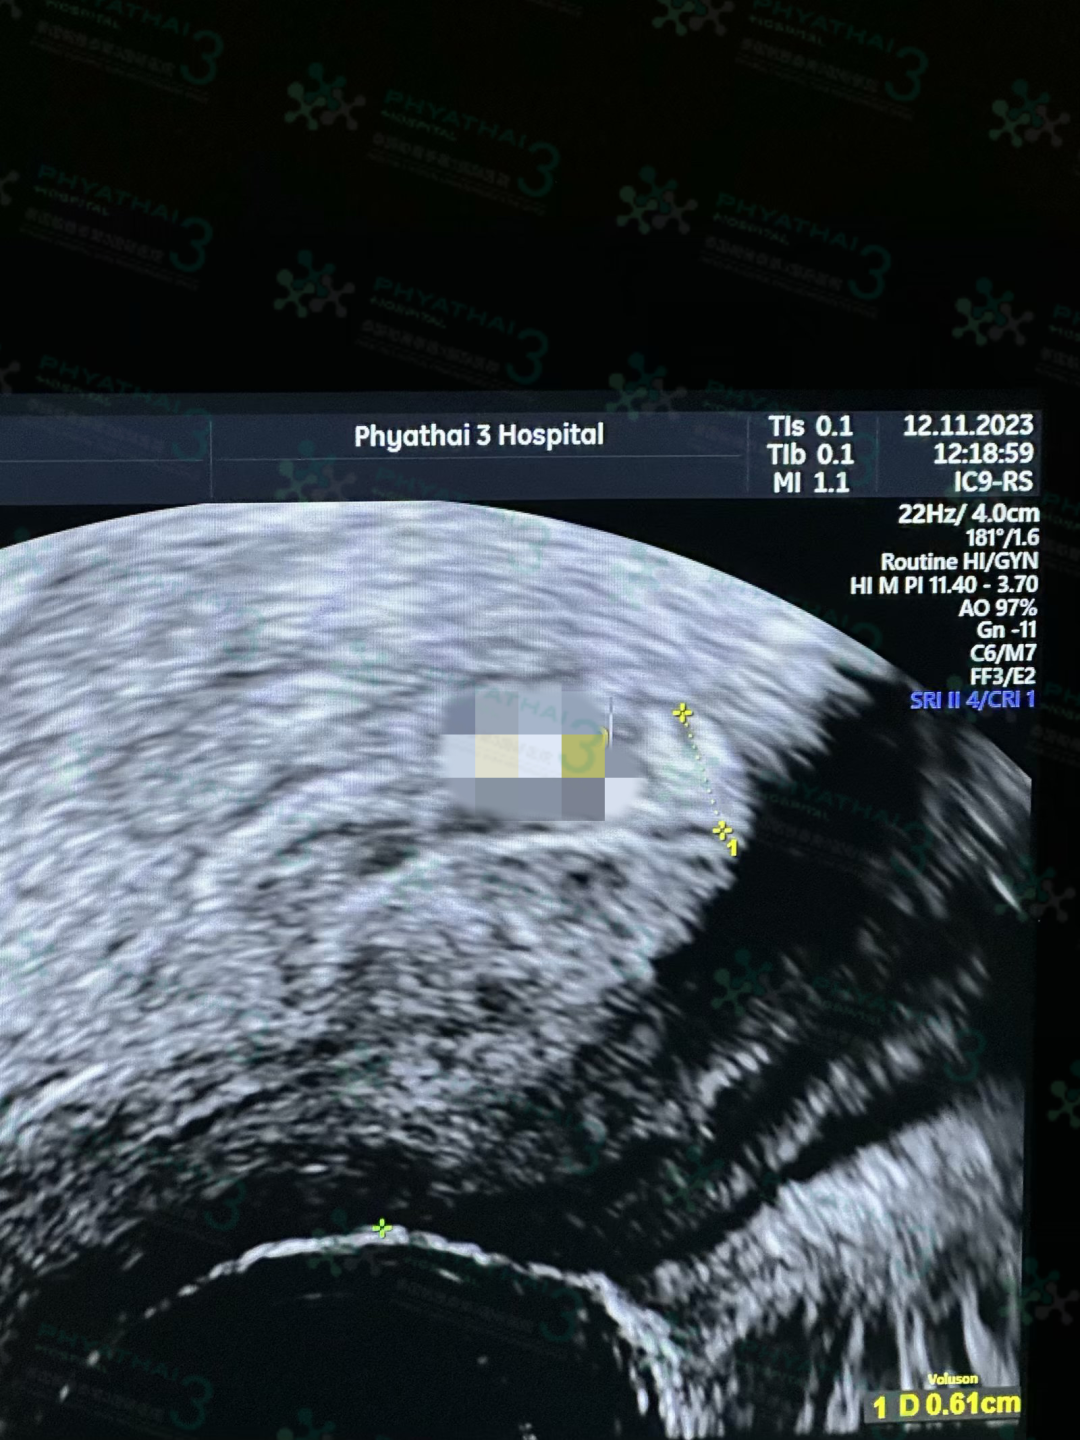

这张照片将成为我们准爸妈珍贵的回忆,记录下这个特别的时刻,现在我们小宝宝就已经开始发育生长器官了,胎心胎动正常,好感动,女士说宝宝正常发育的背后就是我们的努力、爱和家庭的支持,是我们共同的成长和奋斗,所以也希望您早日顺利抱可爱的宝宝在怀抱中的噢

#每日动态发布✅ 最幸福最美妙的声音

我们在泰生活的小姐姐今天来做产检,小宝宝已经19周+6天啦~时间好快,宝宝生长发育的很棒,医生超细致的检查,宝妈说每次检查会有点紧张,但只要听到医生说“正常”两个字瞬间就放心安稳下来

宝宝的心跳声强有力一切发育的都很好,祝福接下来也一切顺利期待宝宝出生